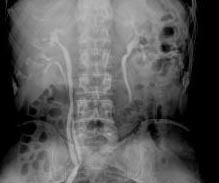

SIGNO DEL CHORRO O JET URETERAL

En urografía intravenosa, no es infrecuente ver una imagen lineal radiodensa correspondiente al chorro de contraste que alcanza la vejiga desde el uréter, visible por la menor densidad del contenido vesical (mezcla de contraste y orina). Este signo indica que el uréter es permeable y excluye, por tanto, obstrucción. Debe diferenciarse de un uréter ectópico, el cual nunca cruza la línea media.

También puede verse el jet ureteral en la TC y en ecografía en tiempo real.